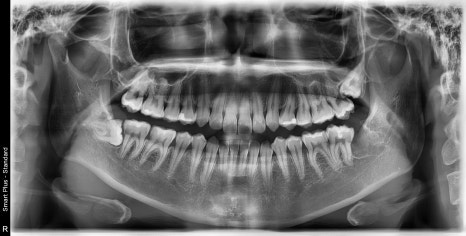

| 발치 전 | 발치 후 |